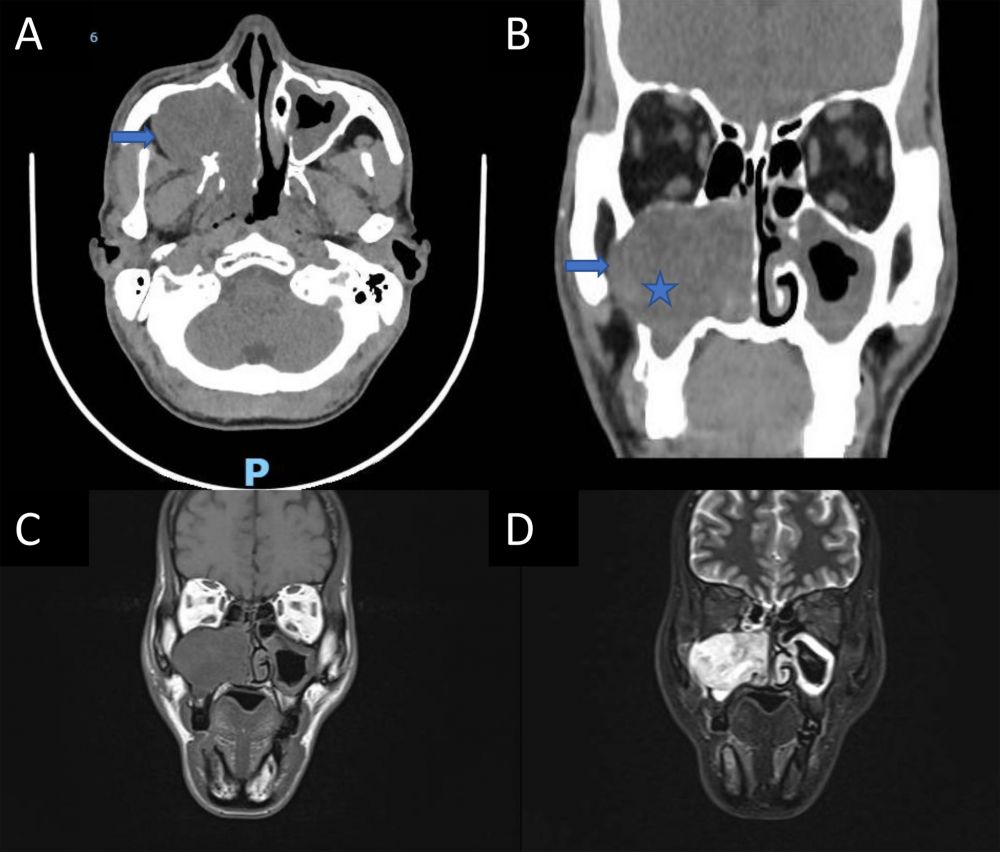

Vừa qua, Khoa Tai Mũi Họng – Mắt - Răng Hàm Mặt, Bệnh viện Trường Đại học Y Dược Huế đã thực hiện phẫu thuật nội soi với đường mổ Denker cải tiến để lấy khối u tế bào quanh mạch mũi xoang cho một bệnh nhân nam 53 tuổi. Bệnh nhân nhập viện vì nghẹt mũi, chảy mũi, giảm khứu giác, đau nhức mặt và chảy nước mắt bên phải trong 6 tháng. Khám nội soi ghi nhận khối u hốc mũi phải đẩy lệch cuốn mũi dưới, chiếm phức hợp lỗ ngách phải, kèm hình ảnh tiêu xương và xâm lấn vào hố dưới thái dương.

Hình 1. Hình ảnh khối u tế bào quanh mạch mũi xoang. A, Hình ảnh chụp cắt lớp vi tính khối u (hình ngôi sao) gây tiêu xương (mũi tên xanh dương); B, Hình ảnh khối u đẩy ổ mắt và xoang hàm; C và D, Hình ảnh cộng hưởng từ khối lan lên xoang sàng và cửa mũi sau